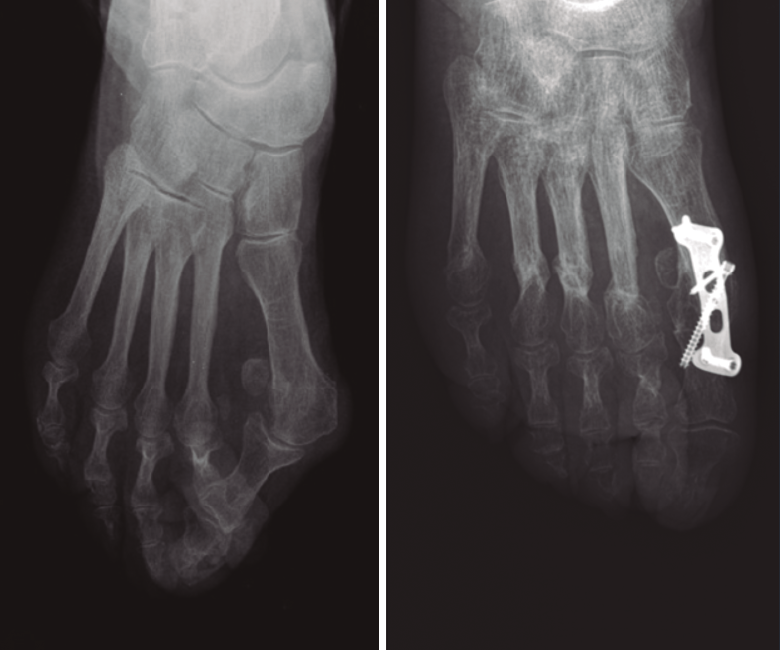

Material y métodos: se revisaron las radiografías de 14 pacientes con HV severo (AIM ≥ 15°) tratados mediante técnica de osteotomía distal metatarsiana asociada a la artrodesis MTF (seguimiento medio: 15 meses). Una revisión independiente realizó las mediciones. Las variables del estudio han sido: el AIM prequirúrgico (AIM preQ), el AIM posquirúrgico (AIM posQ), la diferencia y el cociente de los AIM preQ y AIM posQ. Se han comparado los pacientes con TQC frente a la artrodesis MTF aislada (utilizando series publicadas en la literatura).

Resultados: Grupo A: pacientes de TQC. Grupo B: pacientes tratados con artrodesis MTF aislada. Los AIM preQ son iguales en ambos grupos. Los ángulos posQ en el grupo A son 4,194° y 9,9° en el grupo B (p < 0,001). La TQC logra reducciones del AIM de 14,253° de media en el grupo A frente a los 8,489° de reducción del AIM conseguidos en el grupo B por la artrodesis MTF aislada.

Conclusiones: el tratamiento quirúrgico combinado (osteotomía metatarsiana más artrodesis MTF) consigue mayor corrección radiológica del AIM que la artrodesis MTF aislada.